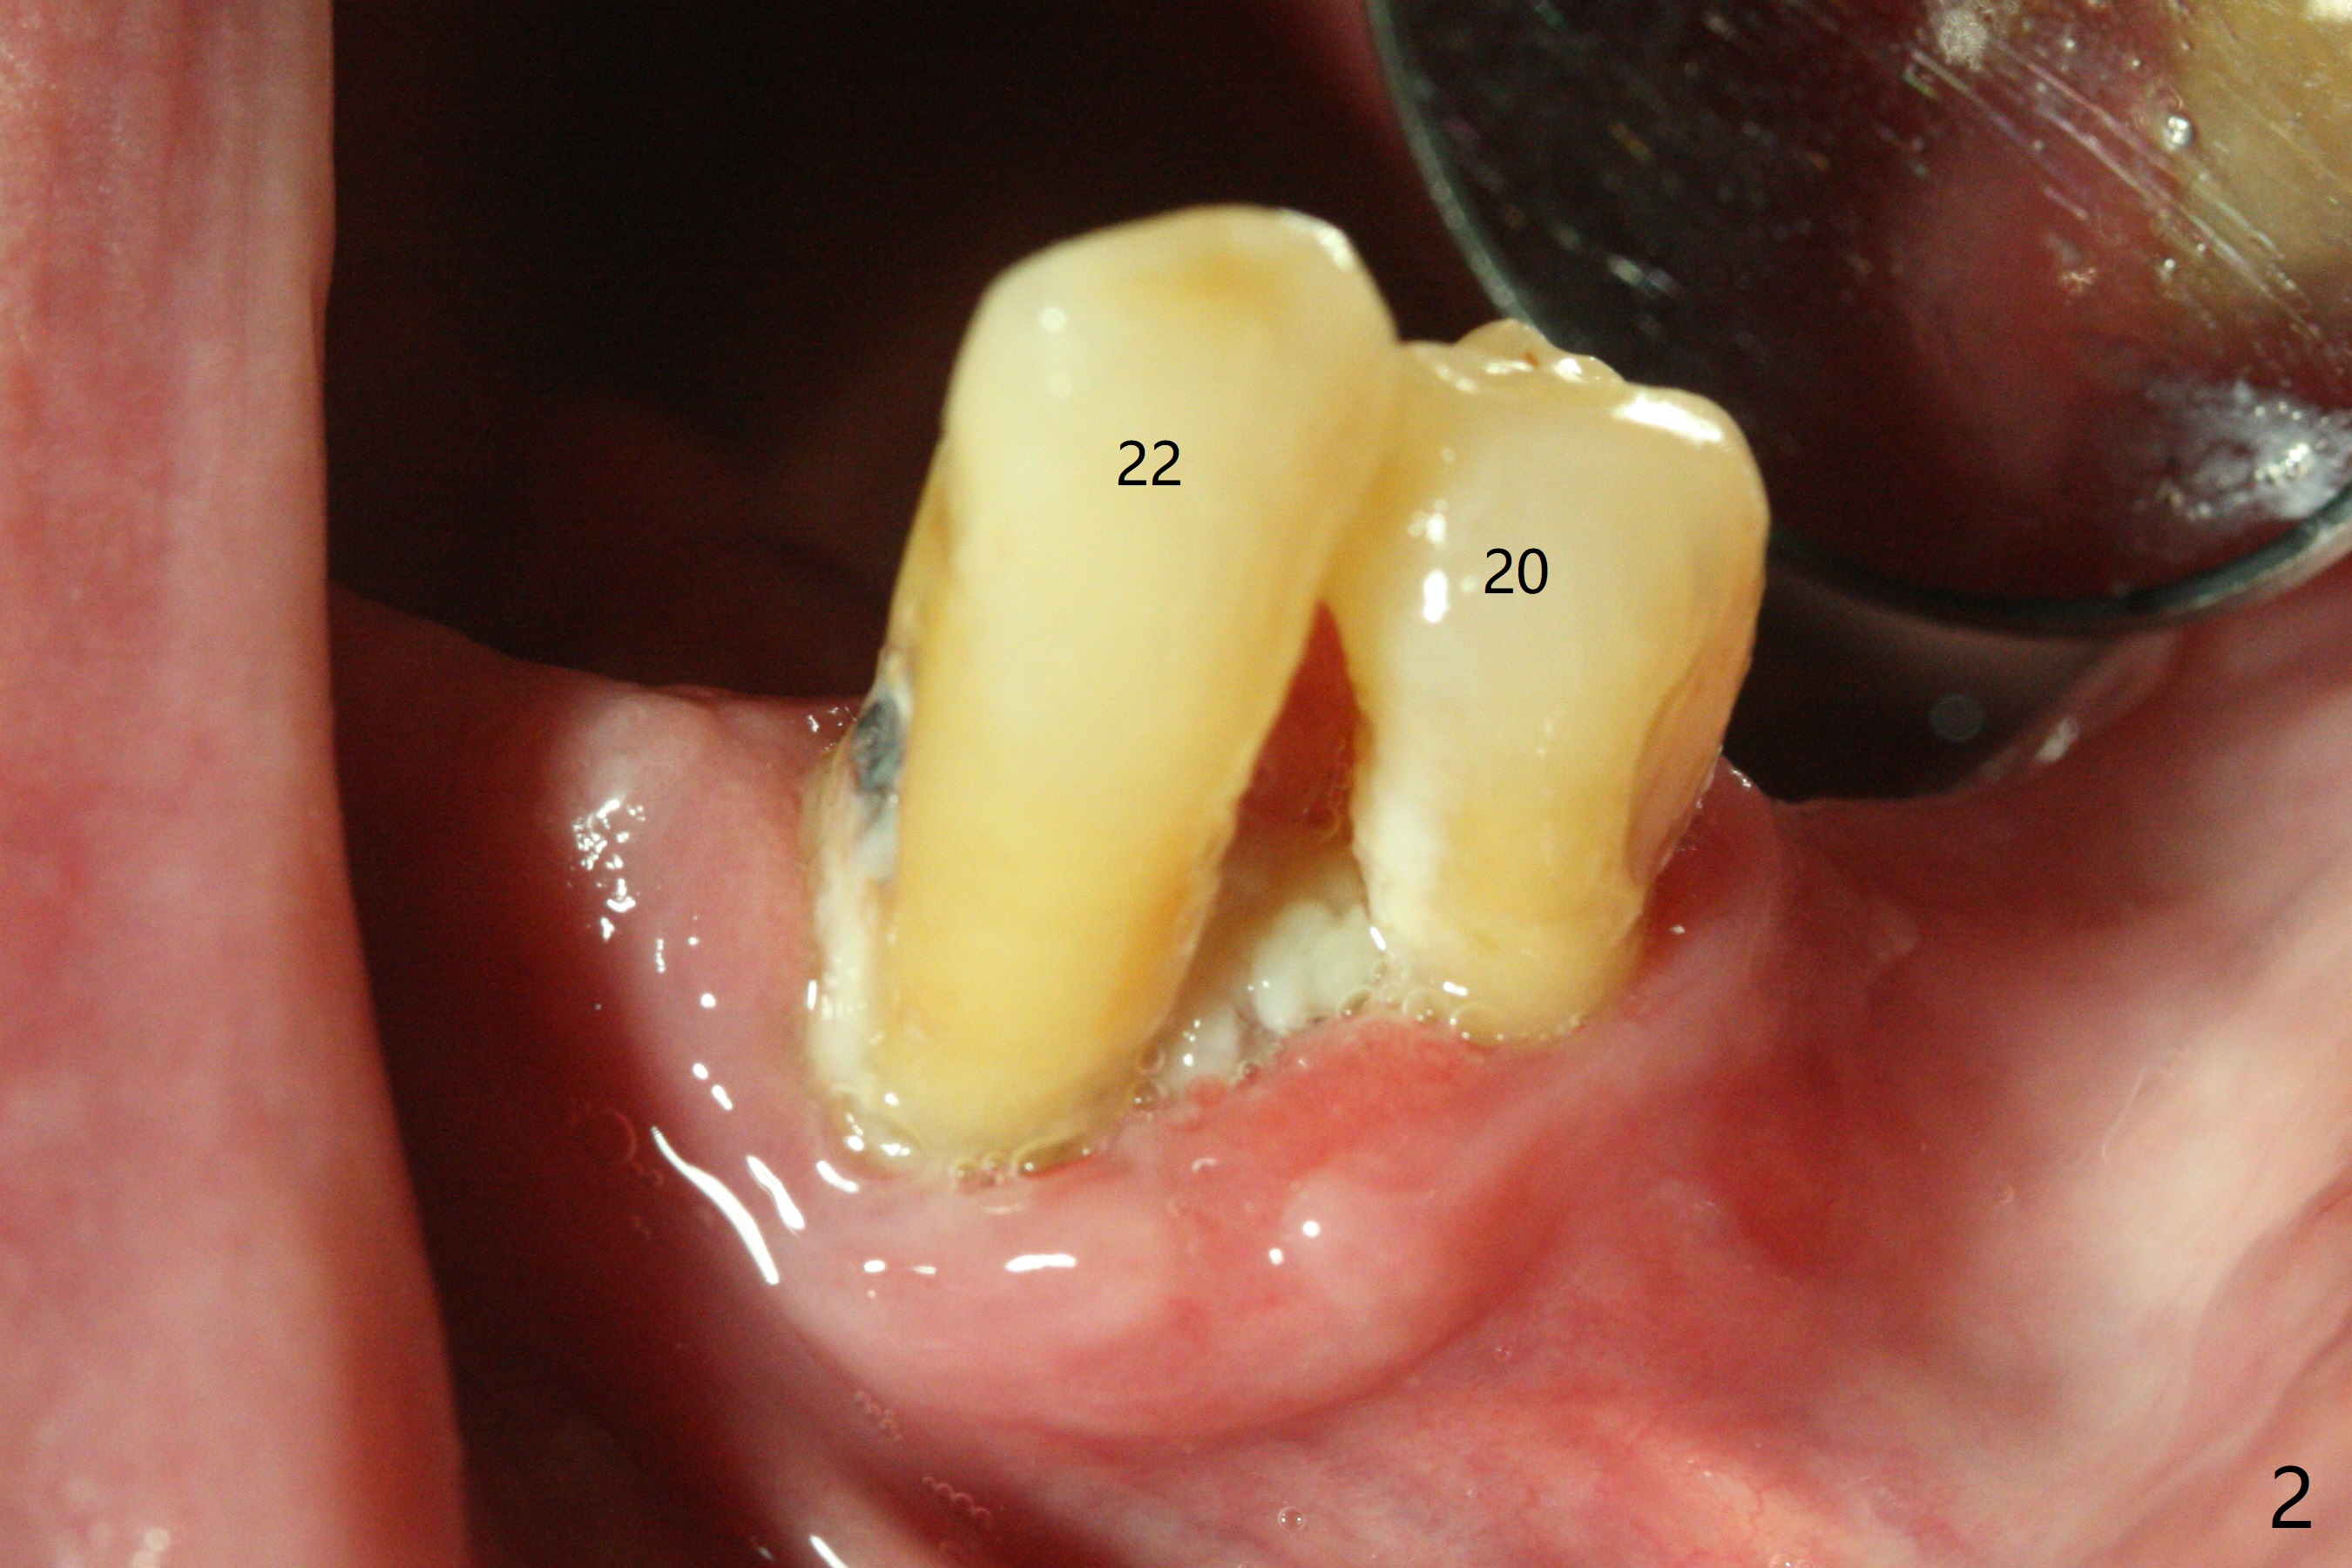

A 84-year-old man (uncontrolled diabetes) requests extraction of terminal teeth (#17, 20-22) for complete denture (Fig.1-3). He does not have finance for implants now. After extraction and debridement, 1 cc of Bond Apatite is applied to the sockets (Fig.4-6). The sockets at #20-22 are primarily closed with 4-0 PGA (Fig.7), while that of #17 with 4-0 Chromic gut suture over Osteogen Plug (a type of Collagen Plug, Fig.8). PGA sutures remain in place (Fig.9,10), while Chromic Gut ones dissolve 7 days postop (Fig.11). The ridge at the extraction sites remains robust 2 months postop (Fig.12). The sockets seem to remain radiopaque 2 months postop (Fig.13).